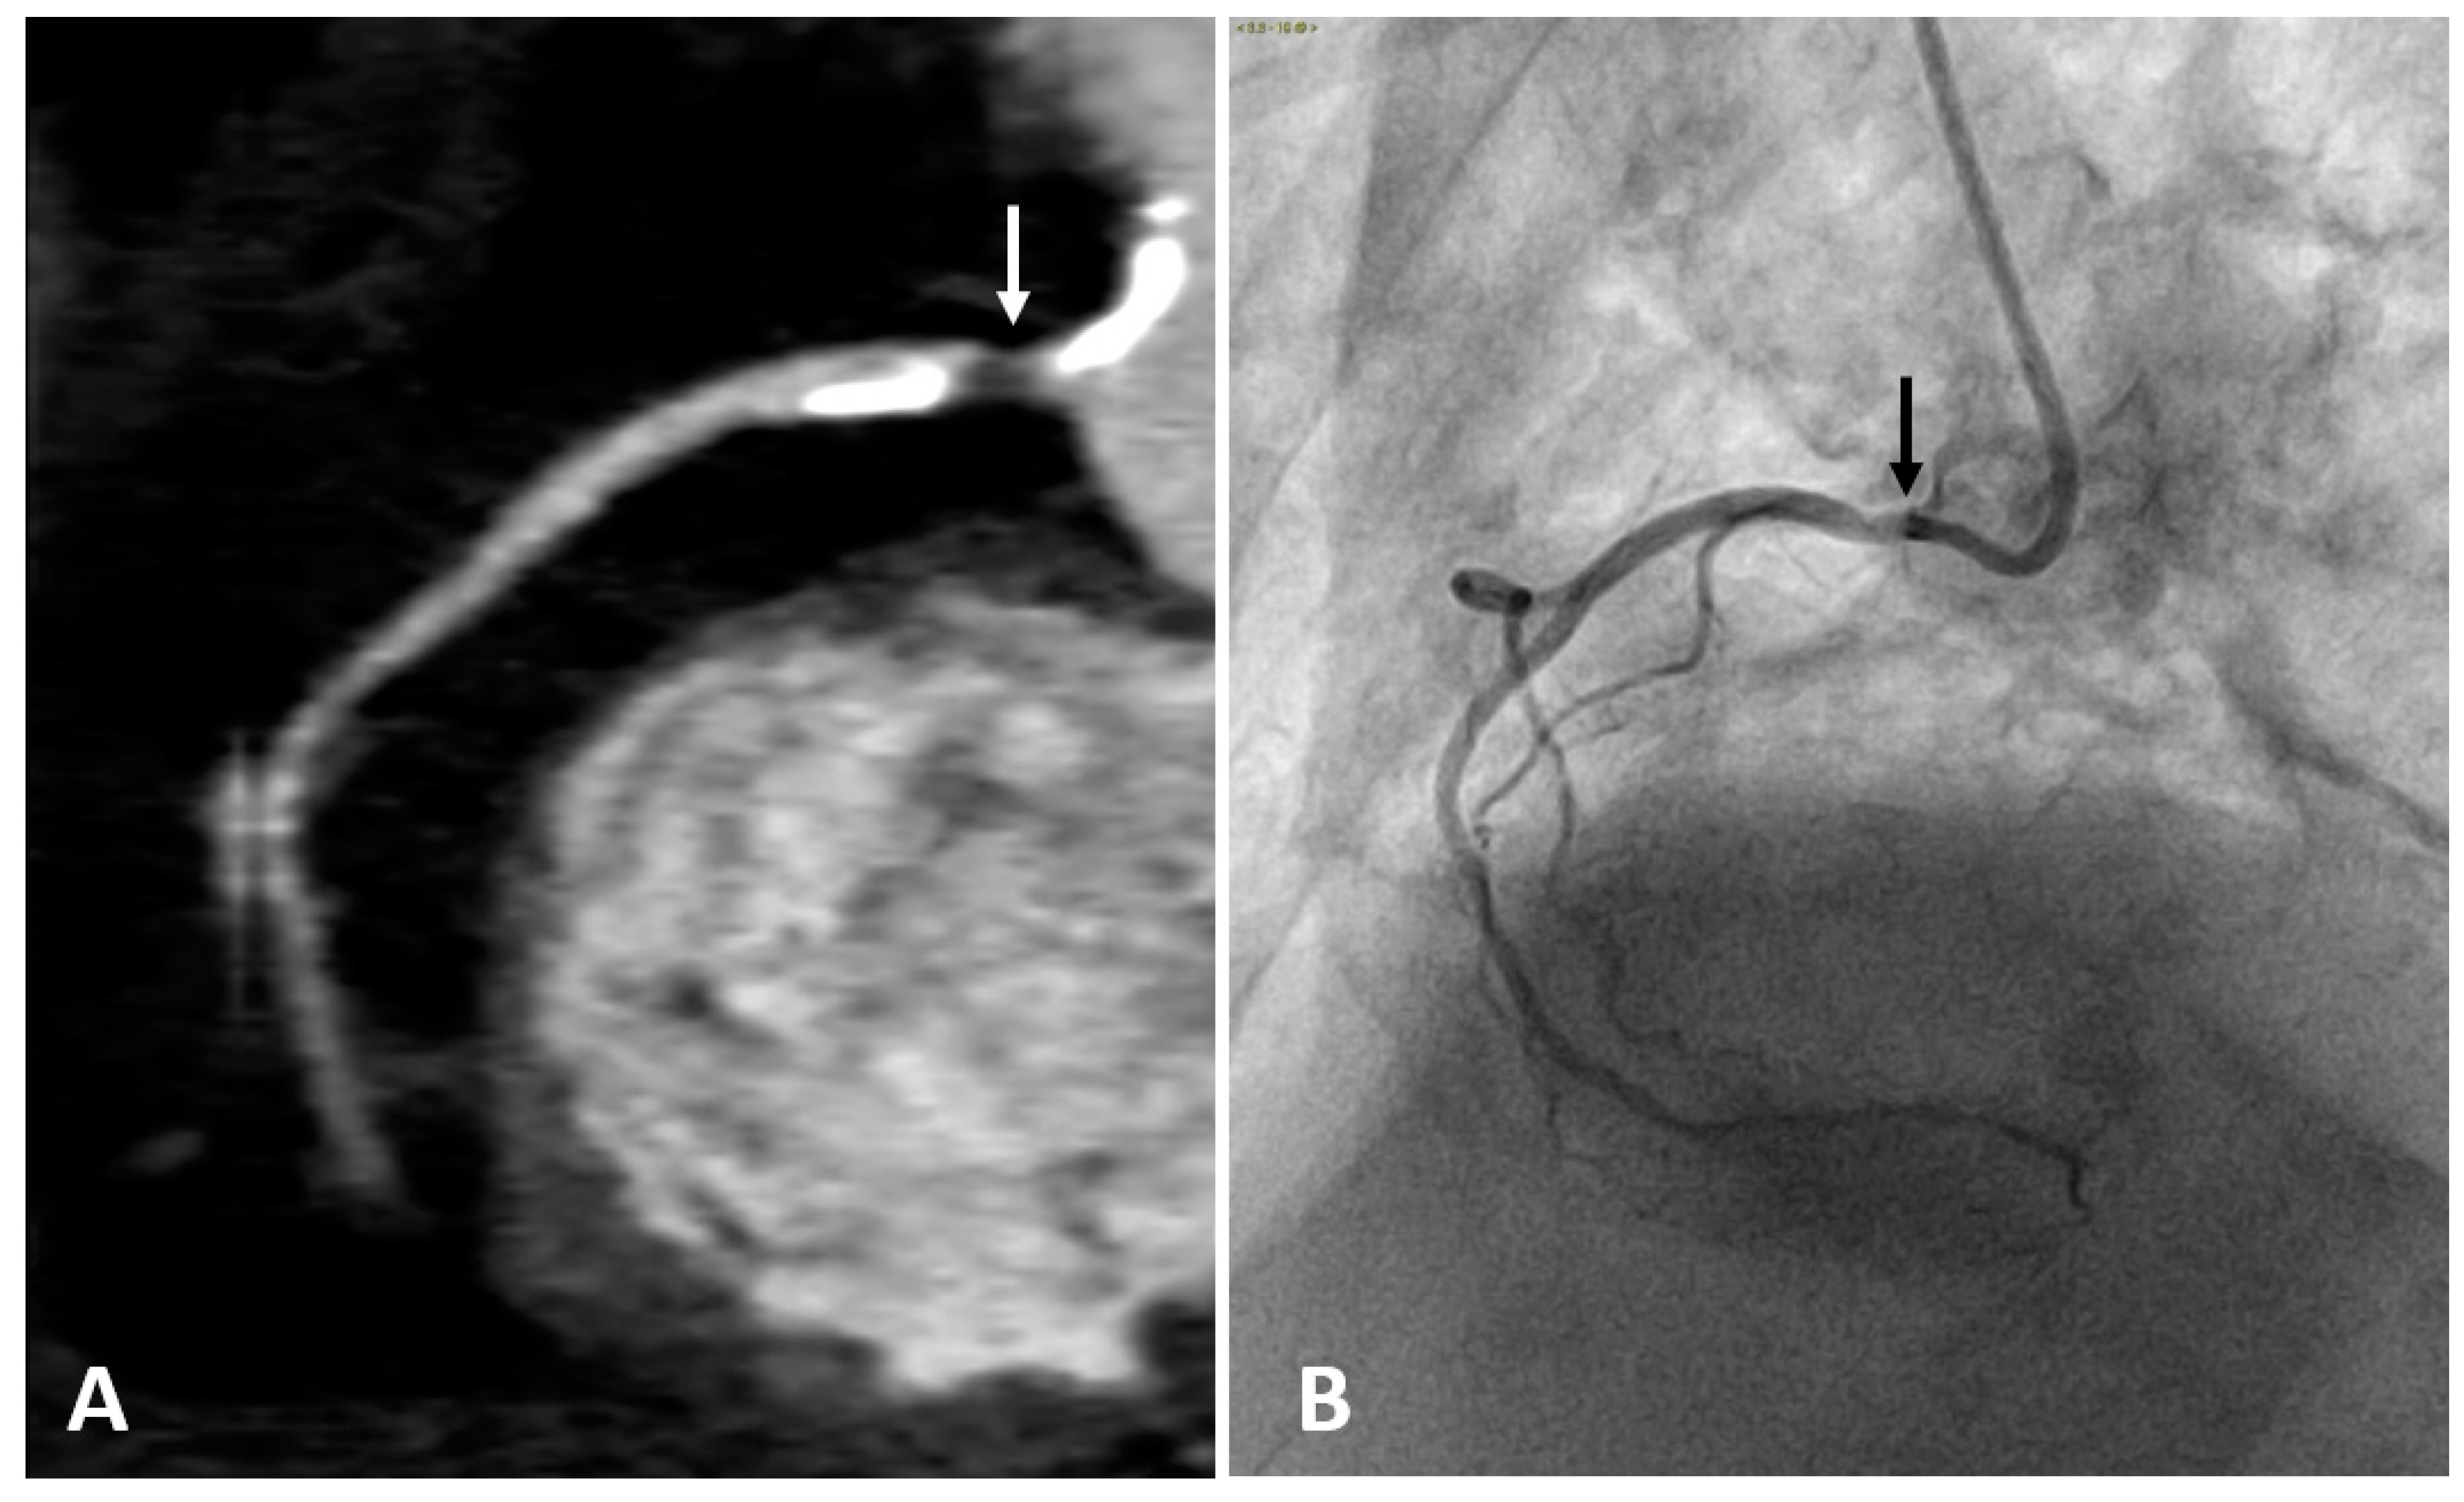

The intravenous administration of iodine contrast media allows the assessment of coronary stenosis and several adverse coronary plaque characteristics, such as spotty calcification, positive remodeling, and low-attenuation non-calcified plaques which identify a large necrotic core [68,69]. (Figure 2 and Figure 3). However, smaller components such as microcalcifications and TCFA cannot be detected because their dimension is ten times lower than the spatial resolution of CTCA (about 500 microns) [70].

Figure 2.

Right coronary artery (RCA) studied with CTCA (A) and with coronary angiography (B) in the same patient. Both examinations show a narrowing of the arterial lumen in the proximal RCA segment (arrows), indicating the presence of an atherosclerotic plaque. CTCA imaging shows a low-attenuation non-calcified plaque which identifies a lipid or necrotic core. Calcifications are hyperdense on CTCA, while not visible on coronary angiography.

Figure 3.

(A) CTCA showing the left main (LM) and left anterior descending (LAD) coronary arteries of a patient who underwent coronary angioplasty (PTCA) and stent positioning in the LM. A non-calcified low density soft plaque (white arrow) is shown between calcific plaques; the hypodense spot (dashed white arrow) within the stent may indicate initial intrastent restenosis. Calcification of the aortic valve leaflets. (B) CTCA of the same patient reformatted in the plane of the aortic valve shows calcification of the aortic leaflets. RVOT: right ventricle outflow tract; LA: left atrium; PA: pulmonary artery.